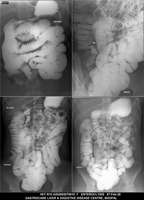

Section: ENTEROCLYSIS

Total: 205 Cases